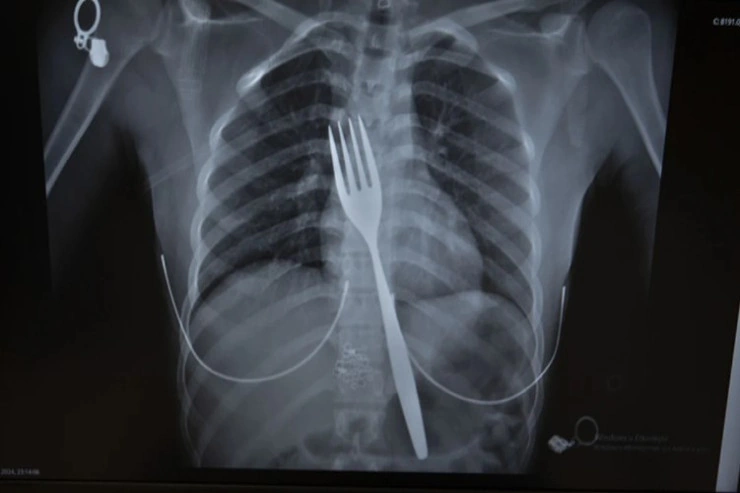

Türkiyənin Aydın vilayətində gənc qızın udduğu 18 santimetrlik çəngəl əməliyyat ilə çıxarılıb.

Burada rentgeni çəkilən xəstənin qida borusunda 18 santimetrlik çəngəl olduğu müəyyən edilib.

Mütəxəssislər endoskopiya edərək çəngəli ağızdan çıxarmağa çalışıblar. Lakin qidaya və nəfəs borusuna zərər vermə ehtimalına görə, mədənin yarılaraq çəngəlin çıxarılması ilə bağlı qərar qəbul olunub.

Həkimlər əməliyyatla mədədəki çəngəli çıxarıbla.